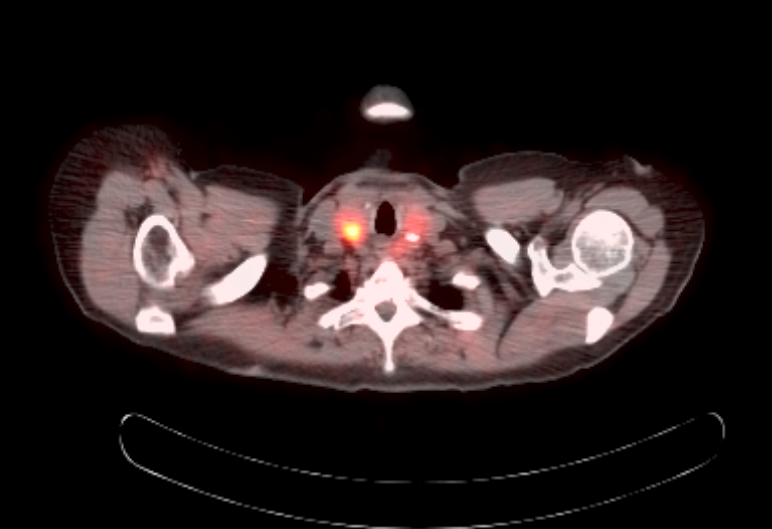

Radiology description

- Anatomical imaging studies: Doppler ultrasonography, CT, MRI, MRA, CT angiography (Cancer Imaging 2012;12:153, Insights Imaging 2019;10:29, Eur J Nucl Med Mol Imaging 2019;46:2112)

- Functional imaging studies: there are 3 types of PET / CT radiopharmaceuticals that exert their actions through different receptors: 18F-FDG, 18F-fluorodopa (18F-FDOPA) and 68Galium(68Ga)-tetraazacyclododecanetetraacetic acid (DOTA) analogs (Front Endocrinol (Lausanne) 2018;9:515)

- Ga 68-DOTATATE PET / CT is the preferred modality, binds to somatostatin receptor (SSTR2) expressed in paragangliomas with a detection rate of 80 - 100%, demonstrating increased uptake in the tumor anatomical location

- See Radiology images